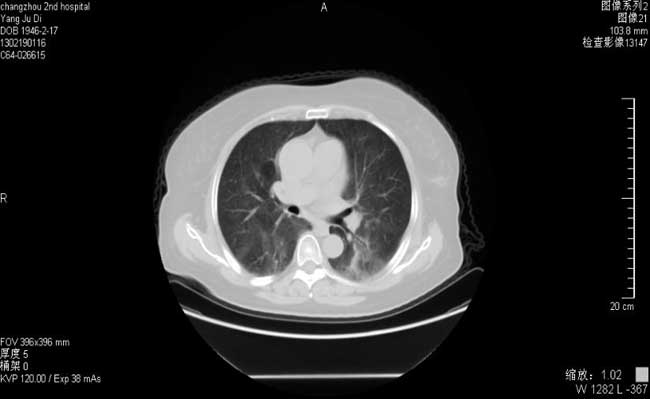

胸部CT:左侧胸壁肿块术后,两肺纹理增多,右肺下叶陈旧灶 。

胸部CT(2013-12)

胸部CT(2013-2-19)

ü肺炎给于左氧氟沙星+美洛西林钠舒巴坦抗感染治疗7天后,体温无好转,患者出现胸闷、气急,查血气分析:PH 7.47HCO329.8mmol/lBE5.6mmol/lSO2 89%,提示低氧血症,予吸氧,复查胸部CT提示肺部感染进展.

更改抗感染药物为拜复乐+SMZ+更昔洛韦,并给予氢化可的松0.1+丙种球蛋白10g*3天,经治疗患者体温正常,胸闷、气急好转,复查胸部CT肺部感染明显吸收。

2013-3-9

间质性肺炎是以弥漫性肺实质、肺泡炎和间质纤维化为基本病理改变,以活动性呼吸困难、CT示双肺磨玻璃样影、肺弥散功能降低和低氧血症为主要临床表现的肺部炎症。